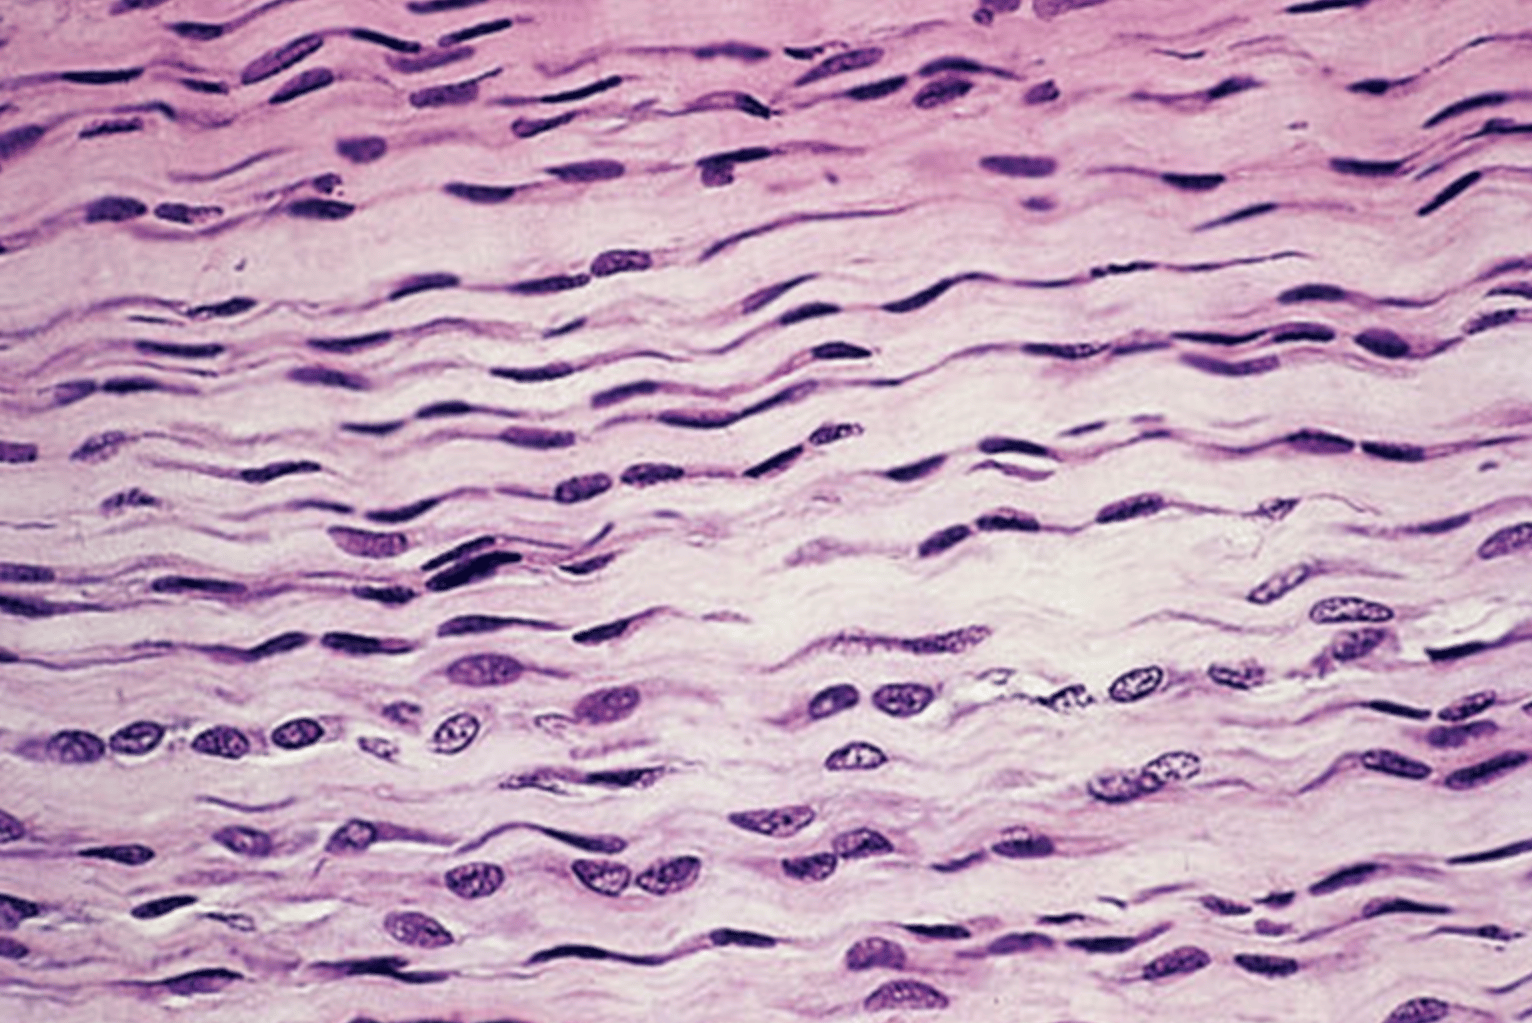

Órgãos do Sistema Tegumentar

O sistema tegumentar é formado pela pele, pelos, unhas e glândulas. Portanto, atua como barreira contra a perda de água e entrada de micro-organismos, e também na regulação da temperatura corporal.

Sendo assim, vamos conhecer mais sobre a pele.

Pele

A pele é o revestimento externo do corpo, sendo o maior e mais pesado órgão do corpo humano. Desse modo, a pele é dividida em duas camadas: derme e epiderme, sendo a derme a camada interna, e a epiderme a camada externa.

Portanto, a principal função da pele é proteger o organismo contra atritos, perda de água excessiva, ação de micro-organismos, raios ultravioletas, entre outros.